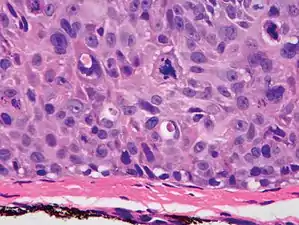

Invasive disease

In invasive cSCC, tumor cells infiltrate through the basement membrane. The infiltrate can be somewhat difficult to detect in the early stages of invasion: however, additional indicators such as full thickness epidermal atypia and the involvement of hair follicles can be used to facilitate the diagnosis. Later stages of invasion are characterized by the formation of nests of atypical tumor cells in the dermis, often with a corresponding inflammatory infiltrate.[12]

High magnification demonstrates the pleomorphism of the invading keratinocytes[12]